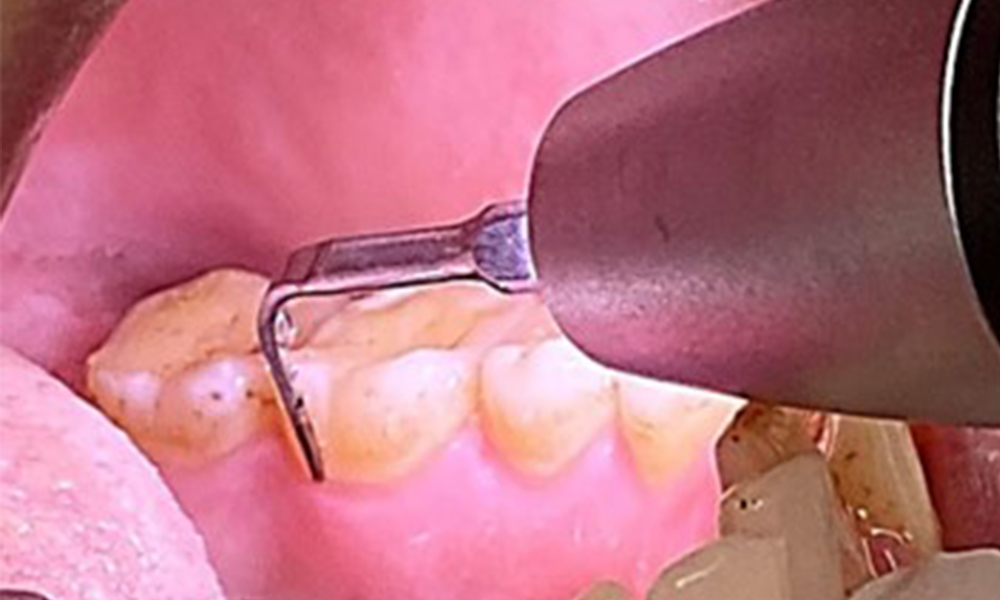

En raison d'un état de santé général par ailleurs favorable, les besoins déterminés lors de l'examen intra-oral seront déterminants pour le traitement. Il sera essentiel de déterminer périodiquement les profondeurs de sondage. Le saignement gingival diminue chez les fumeurs, c'est pourquoi le diagnostic clinique de la parodontite ne peut se faire que par sondage (Fig. 7). En se concentrant exclusivement sur la détermination des indices de saignement, on risque d'occulter une parodontite ou une gingivite existante. (5)

L'objectif serait de contrôler le risque de maladie en éliminant le biofilm supra-gingival et sous-gingival. Les instruments peuvent être sélectionnés en fonction des besoins du patient. Tout d'abord, le tartre et les concrétions doivent être éliminés à l'aide d'instruments ultrasoniques et/ou manuels (Fig. 10).